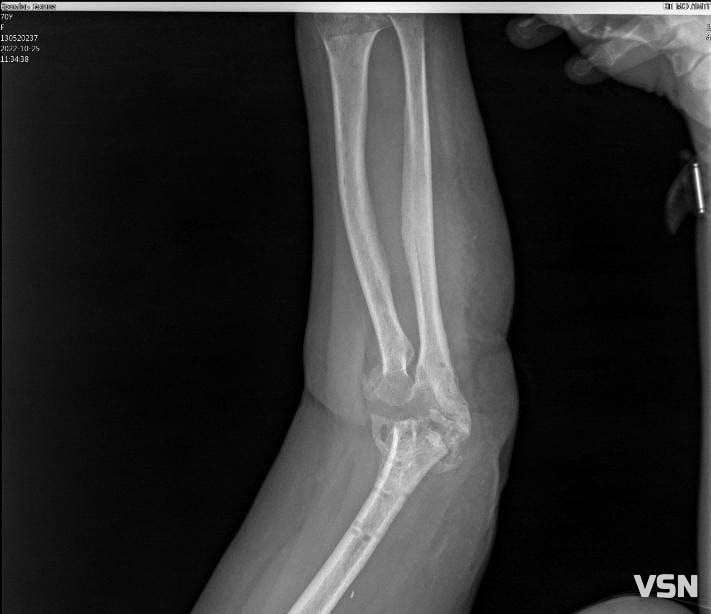

В травні минулого року, поспішаючи на роботу, Галина Кремінь впала та зламала руку, розтрощивши ліктьовий суглоб. Лікарі зробили операцію та вставили пластини, але приєдналась інфекція. Чекаючи зрощення, медики протягом чотирьох місяців рану чистили, обрізали, промивали. Проте, почався остеомієліт. Ще раз прооперували, повиймали пластини та весь метал, почистили кістки. Але суглоб встиг зіпсуватися, і тепер потребує заміни.